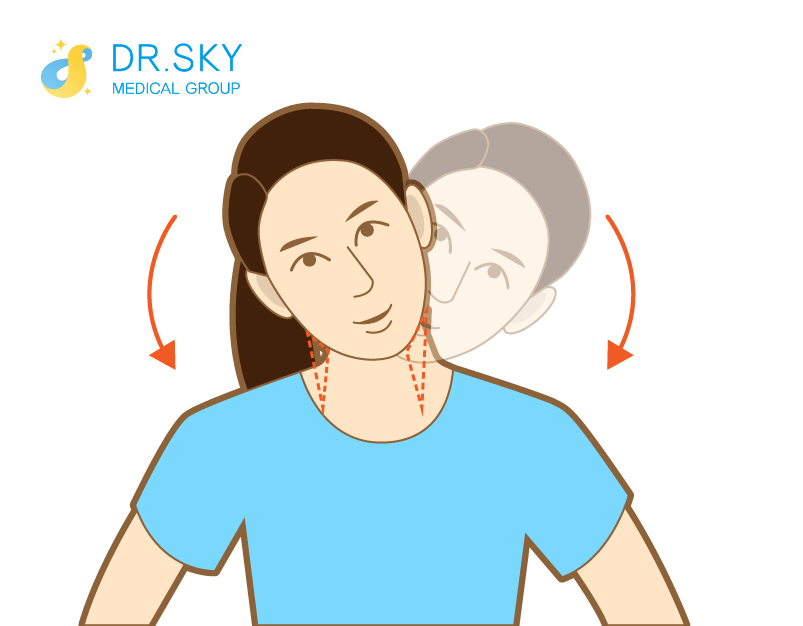

● 積極鍛鍊

可緩解筋肉疲勞,使肌肉韌度變好,有利於增強頸肩順應頸部動態變化的能力。

▲ 側彎運動:頭部傾斜,耳朵靠近肩膀維持15秒後回復起始姿勢。再換另一側,每一側做5次。